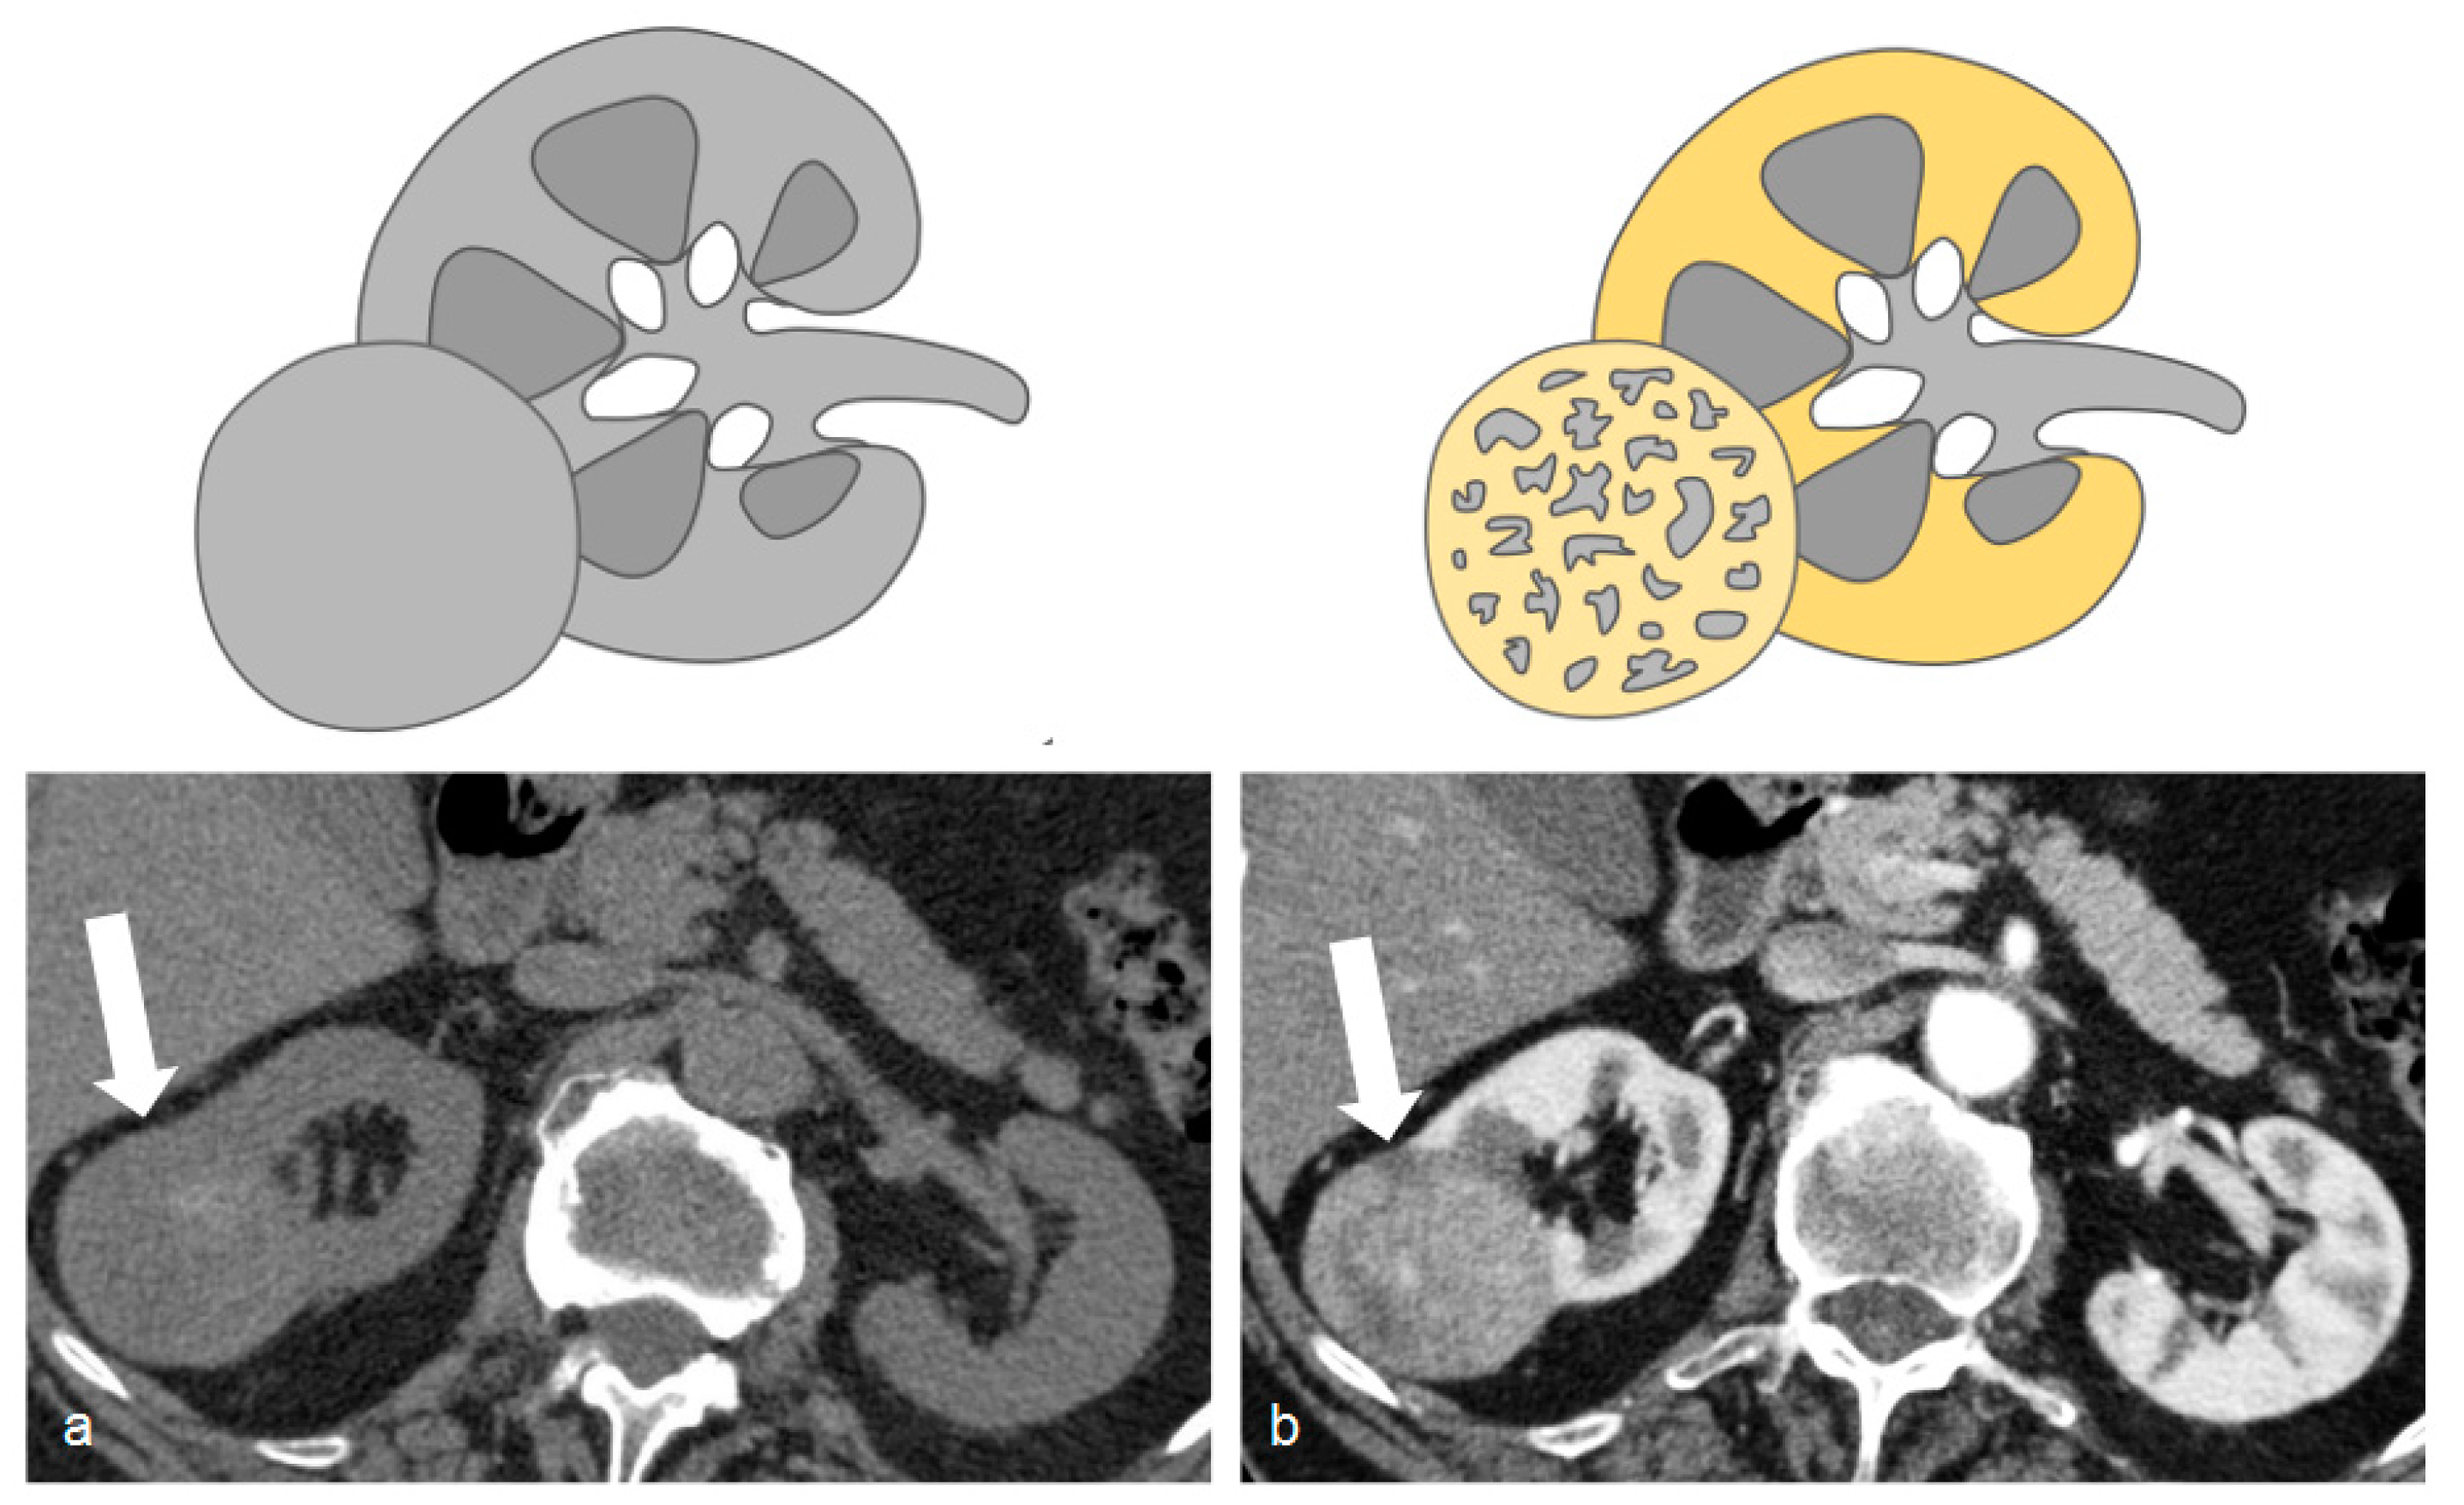

Figure 2.

Unenhanced (a) and arterial post-contrastographic phase (b) showing the presence of a right clear cell carcinoma (white arrows), isodense compared to the renal parenchyma in the unenhanced phase (a), and characterized by vivid contrast enhancement in the arterial phase (b).